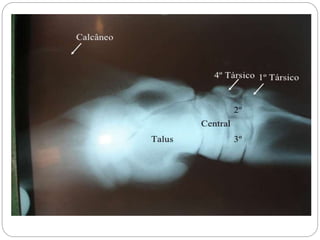

Cervicais (7) C1a C7 Toráxicas (13) T1 a T13 Lombares (7) L1 a L7 Sacras (3) São unidas e formam o osso Sacro Coccigeas (13 a 21) Co1 a Co13 ou Co21 formam a cauda Costelas (13 pares) 9 chamadas de verdadeiras e 4 de flutuantes Esqueleto apendicular Membro Anterior Escápula Úmero (braço) Rádio (antebraço) Carpo (joelho) Metacarpo (canela) Falanges (dedos) Membro posterior (pélvico) Coxal (Ísquio, Íleo e Púbis) (bacia) Fêmur (coxa) Paleta (rótula) Tíbia (perna) Perônio (perna) Tarso (jarrete) Metatarso (canela) Falanges (dedos)